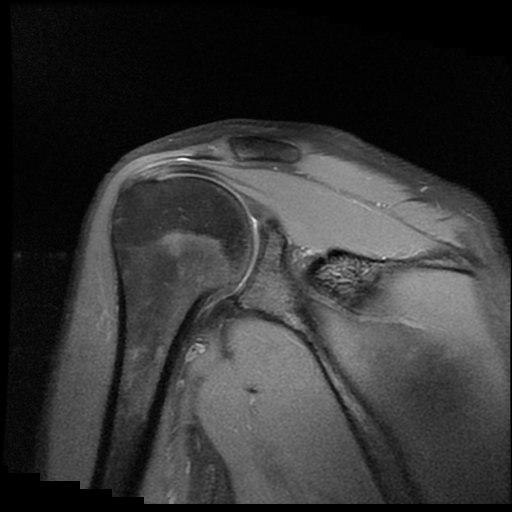

TECNICA EMPLEADA

Se coloca al paciente en decúbito supino, utilizando bobina dedicada de 8 canales, obteniendo imágenes en planos axial, sagital y coronal, secuencias, Spin Echo, Eco de Gradiente, potenciadas a Densidad de Protones, con pulsos de saturación de grasa.

HALLAZGOS IMAGENOLOGICOS

Lesión post traumática de Hill Sachs a nivel de la cabeza humeral, tendinosis aguda del supra espinoso.